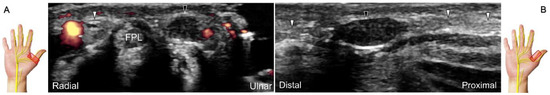

Chronic irritation may lead to the formation of a neuroma, which can occasionally be detected through US imaging (Figure 31). Using the in-plane approach in short-axis view (Figure 32, Video S4), hydrodissection of the entrapped nerves can be performed after identifying the palmar common digital artery and flexor digitorum superficialis/profundus tendons.

Figure 31. Sonographic imaging of the neuroma of the palmar proper digital nerve in short-axis (A) and long-axis (B) views. White arrowheads: normal segments of the palmar proper digital nerve; black arrowhead: neuroma. FPL: flexor pollicis longus tendon.